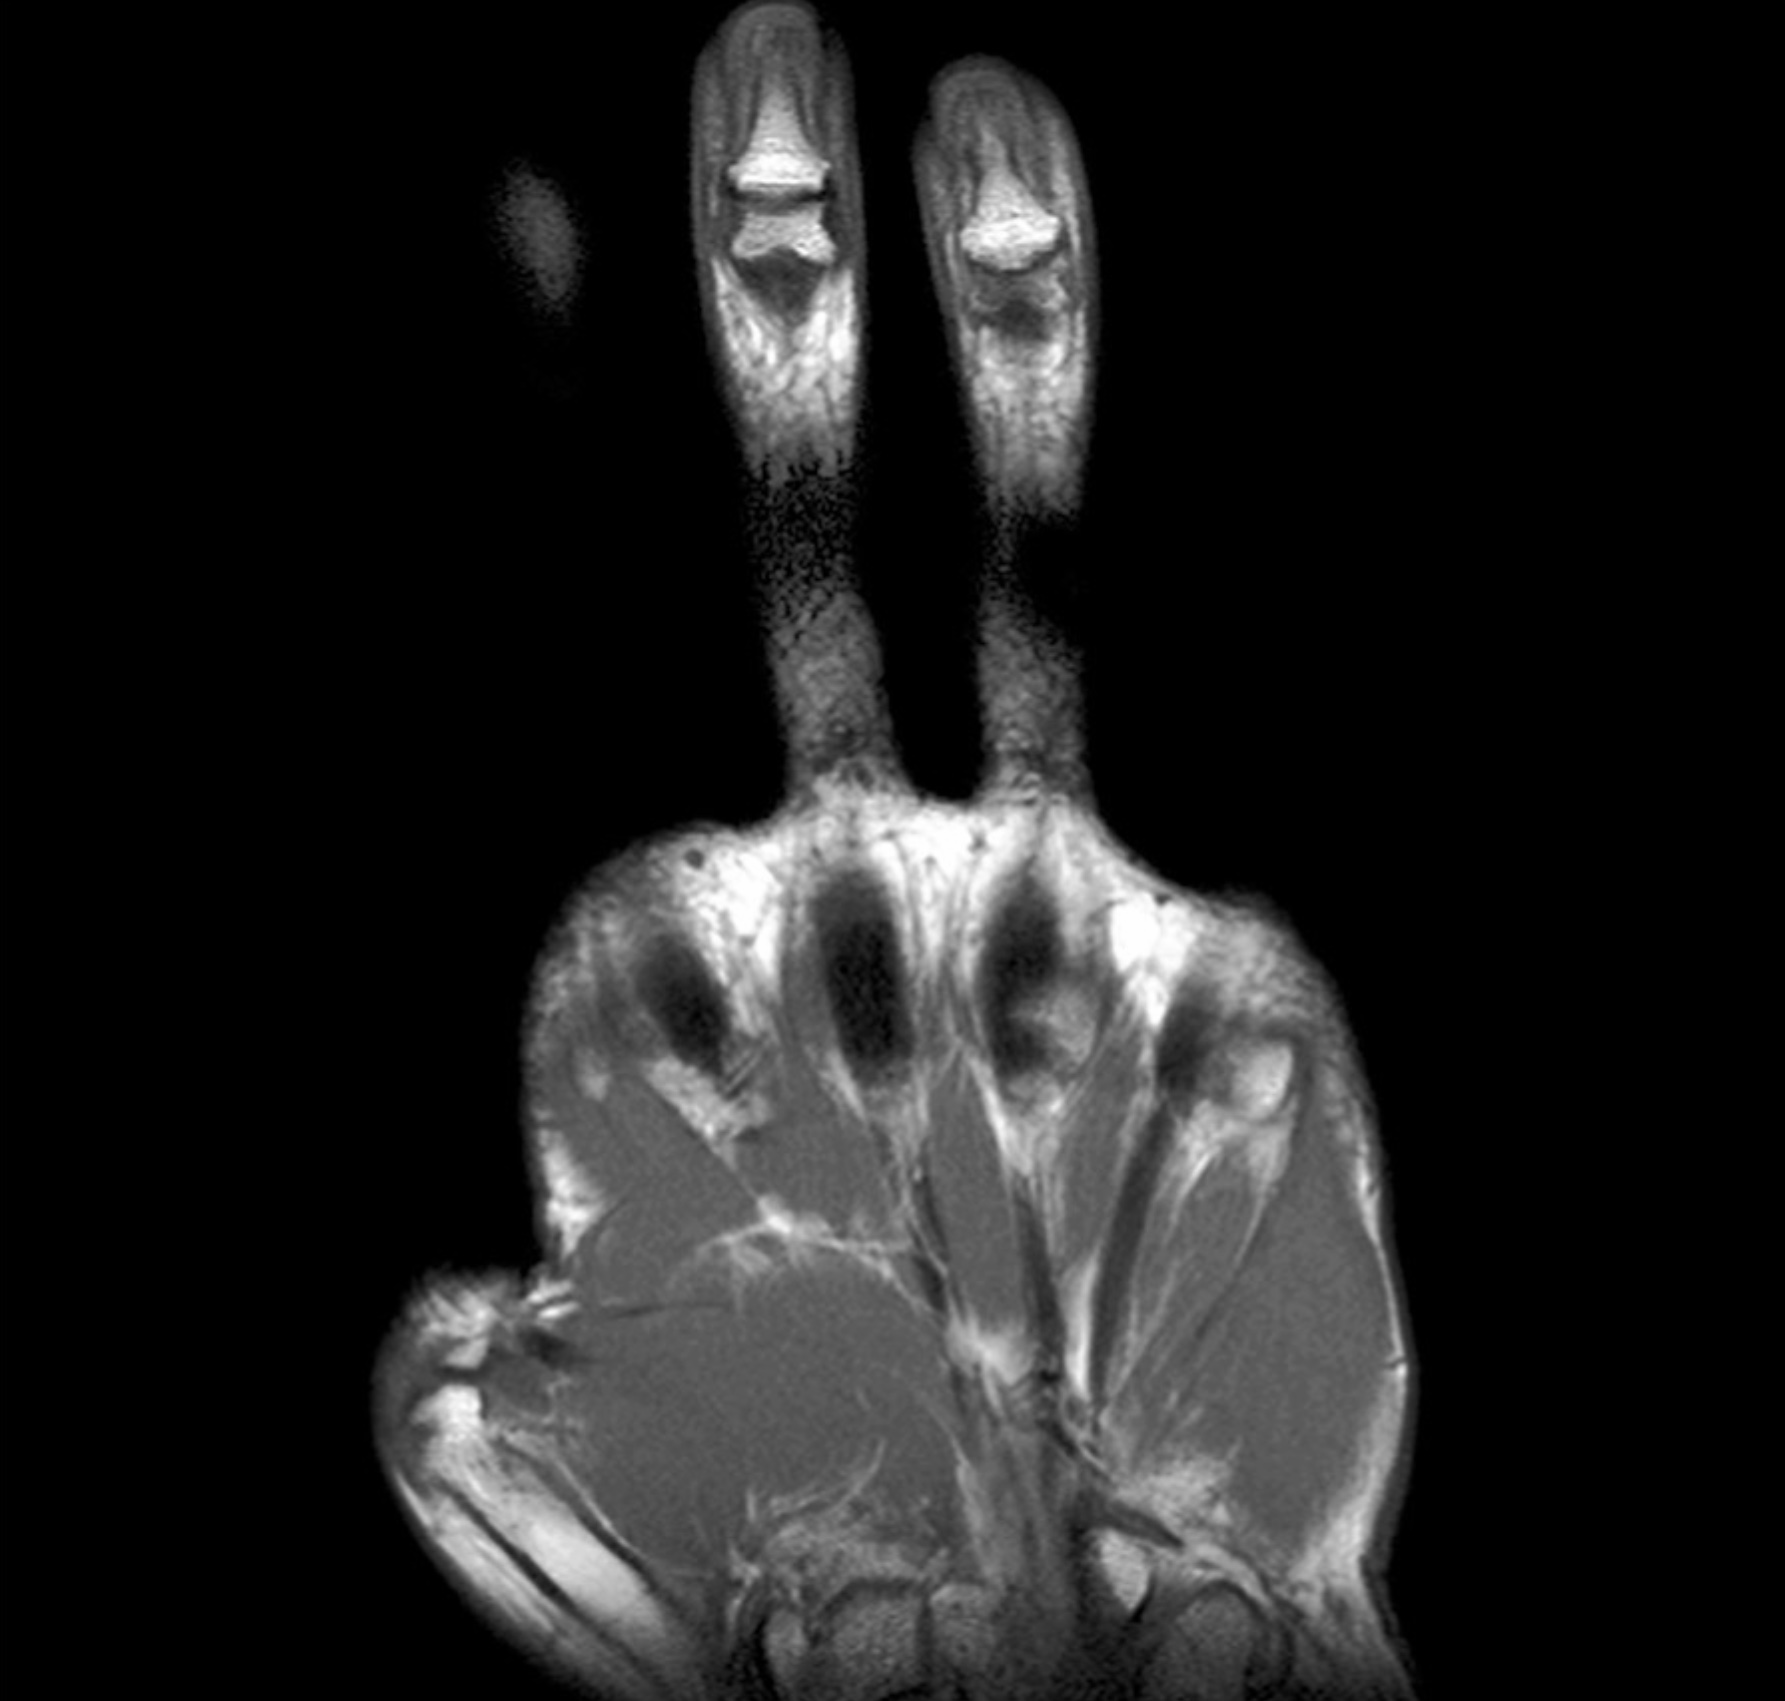

Lecture 27: Palm of Hand - Dr. Evey and G. Francis

1. 34-yr-old male presents to the clinic with diminished sensation and paresthesia of the medial 1.5 digits. The patient just returned from a long distance cycling race. Describe the anatomy of Guyon’s canal. What major motor deficits would the patient present with for compression of Guyon’s canal? Include in your answer the named branches of the nerve involved and why the patient would be able to perceive sensation for the majority of the dorsum of the hand, but have diminished sensation for the nailbeds of the medial 1.5 digits. (G. Francis)

2. Discuss the anatomy of the palm; including boundaries, contents, musculature, vascular supply, innervation, lymphatics and relationships.

3. Discuss the anatomy of the thenar eminence; including boundaries, contents, musculature and movements, vascular supply, innervation, lymphatics and relationships.

True/False. 1 Point Each.

1. All but five intrinsic muscles of the hand are innervated by the ulnar nerve. (True)

2. The lumbricals and interossei act synergistically to flex the metacarpal phalangeal joint while holding the interphalangeal joints in extension. (True)

3. Injury to the ulnar nerve within the cubital tunnel causes less clawing of the fingers than does ulnar nerve injury within the ulnar canal (Guyon canal). (True)

4. Injury to the recurrent median nerve, in time, causes the appearance of ape hand. (True)

5. Dorsal interossei are bipennate and palmar interossei are unipennate. (True)

6. The palmar proper digital nerves supply the dorsum of the fingers at the nail beds. (True)

7. The surface projection of the superficial palmar arch is distal to the projection of the deep palmar arch. (True)

arrowbup Top arrowbdown Bottom